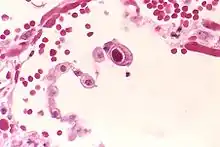

Cytomegalovirus

Cytomegalovirus (CMV) er en virusinfektion, som de fleste mennesker får, inden de er fyldt 50 år. De fleste har ingen eller kun lette symptomer, som om man har en let influenza, når de bliver smittet. Hos raske personer er der typisk ikke nogle symptomer.